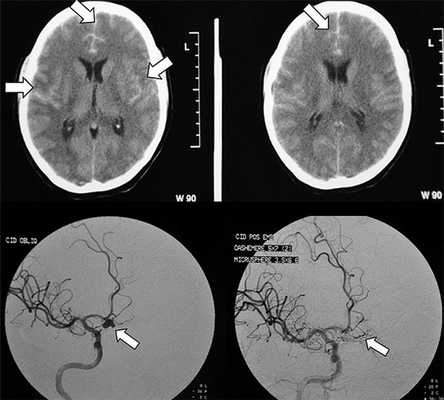

Рисунок 2. Как выглядит субарахноидальное кровоизлияние на диагностическом снимке. Источник:Brazilian Journal of Psychiatry (Creative Commons Attribution Non-Commercial License)

- Компьютерная томография помогает определить стадию САК, его выраженность и выявить наличие крови в желудочках мозга или веществе мозга.

- Церебральная ангиография сосудов головного мозга. Введение в сосуды контрастного вещества позволяет исключить или подтвердить наличие аневризмы, стеноз сосудов и другую патологии церебральных сосудов.

Заподозрить субарахноидальное кровоизлияние неврологу позволяет типичная клиническая картина. В случае атипичных форм ранняя диагностика САК представляется весьма затруднительной. Всем пациентам с подозрением на субарахноидальное кровоизлияние показана КТ головного мозга. Метод позволяет достоверно установить диагноз в 95% САК; выявить гидроцефалию, кровотечение в желудочки, очаги церебральной ишемии, отек мозга.

- Визуализирующие методики. Обнаружение крови под паутинной оболочкой является показанием к церебральной ангиографии с целью установления источника кровотечения. Проводится современная неинвазивная КТ или МРТ-ангиография. У пациентов с наиболее тяжелой степенью САК ангиография осуществляется после стабилизации их состояния. Если источник кровотечения не удается определить, то рекомендуется повторная ангиография через 3-4 нед.